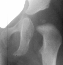

A ten year old female presented with a left hip dislocation. She was born by Cesarean-section because of slow progression of labor. The child was not breech and was noted to have a dislocatable hip at birth. There was a negative family history of DDH. An X-ray prior to application of the brace showed the dislocation of the hip. The patient was first seen at AIDI on 9th day. Abduction of the right hip was 80 degrees but left was only 60 degrees. There was a positive Galeazzi sign with the left hip being shorter than the right. X-rays showed a left hip dislocation and right hip subluxation . A Pavlik harness was applied. After two months, the right hip improved but the left hip was still dislocatable. For this, home traction was started. Even after 2 months, the left hip did not reduce. Therefore, an arthrogram, adductor tenotomy and closed reduction was done at 4 months of age. Single hip spica was applied with the hip in 40 abduction and 100 flexion. Eight weeks later an arthrogram was performed and the cast was reapplied with the hip in 35 degrees abduction and 100 degrees flexion.

Four months later, the spica cast was removed and an Atlanta brace was applied. X-rays showed avascular necrosis at ten months of age . At two years of age, the ossification of the left nucleus was still delayed. The leg lengths were equal and the range of motion of the hip was full.

The progression of the hip is documented by x-rays taken at 1 year of age, 2 years of age, 3 years of

age, 5 years of age, 7 years of age, then at ten years of age, early closure of the lateral portion of proximal growth plate observed. Coxa valga was also observed.